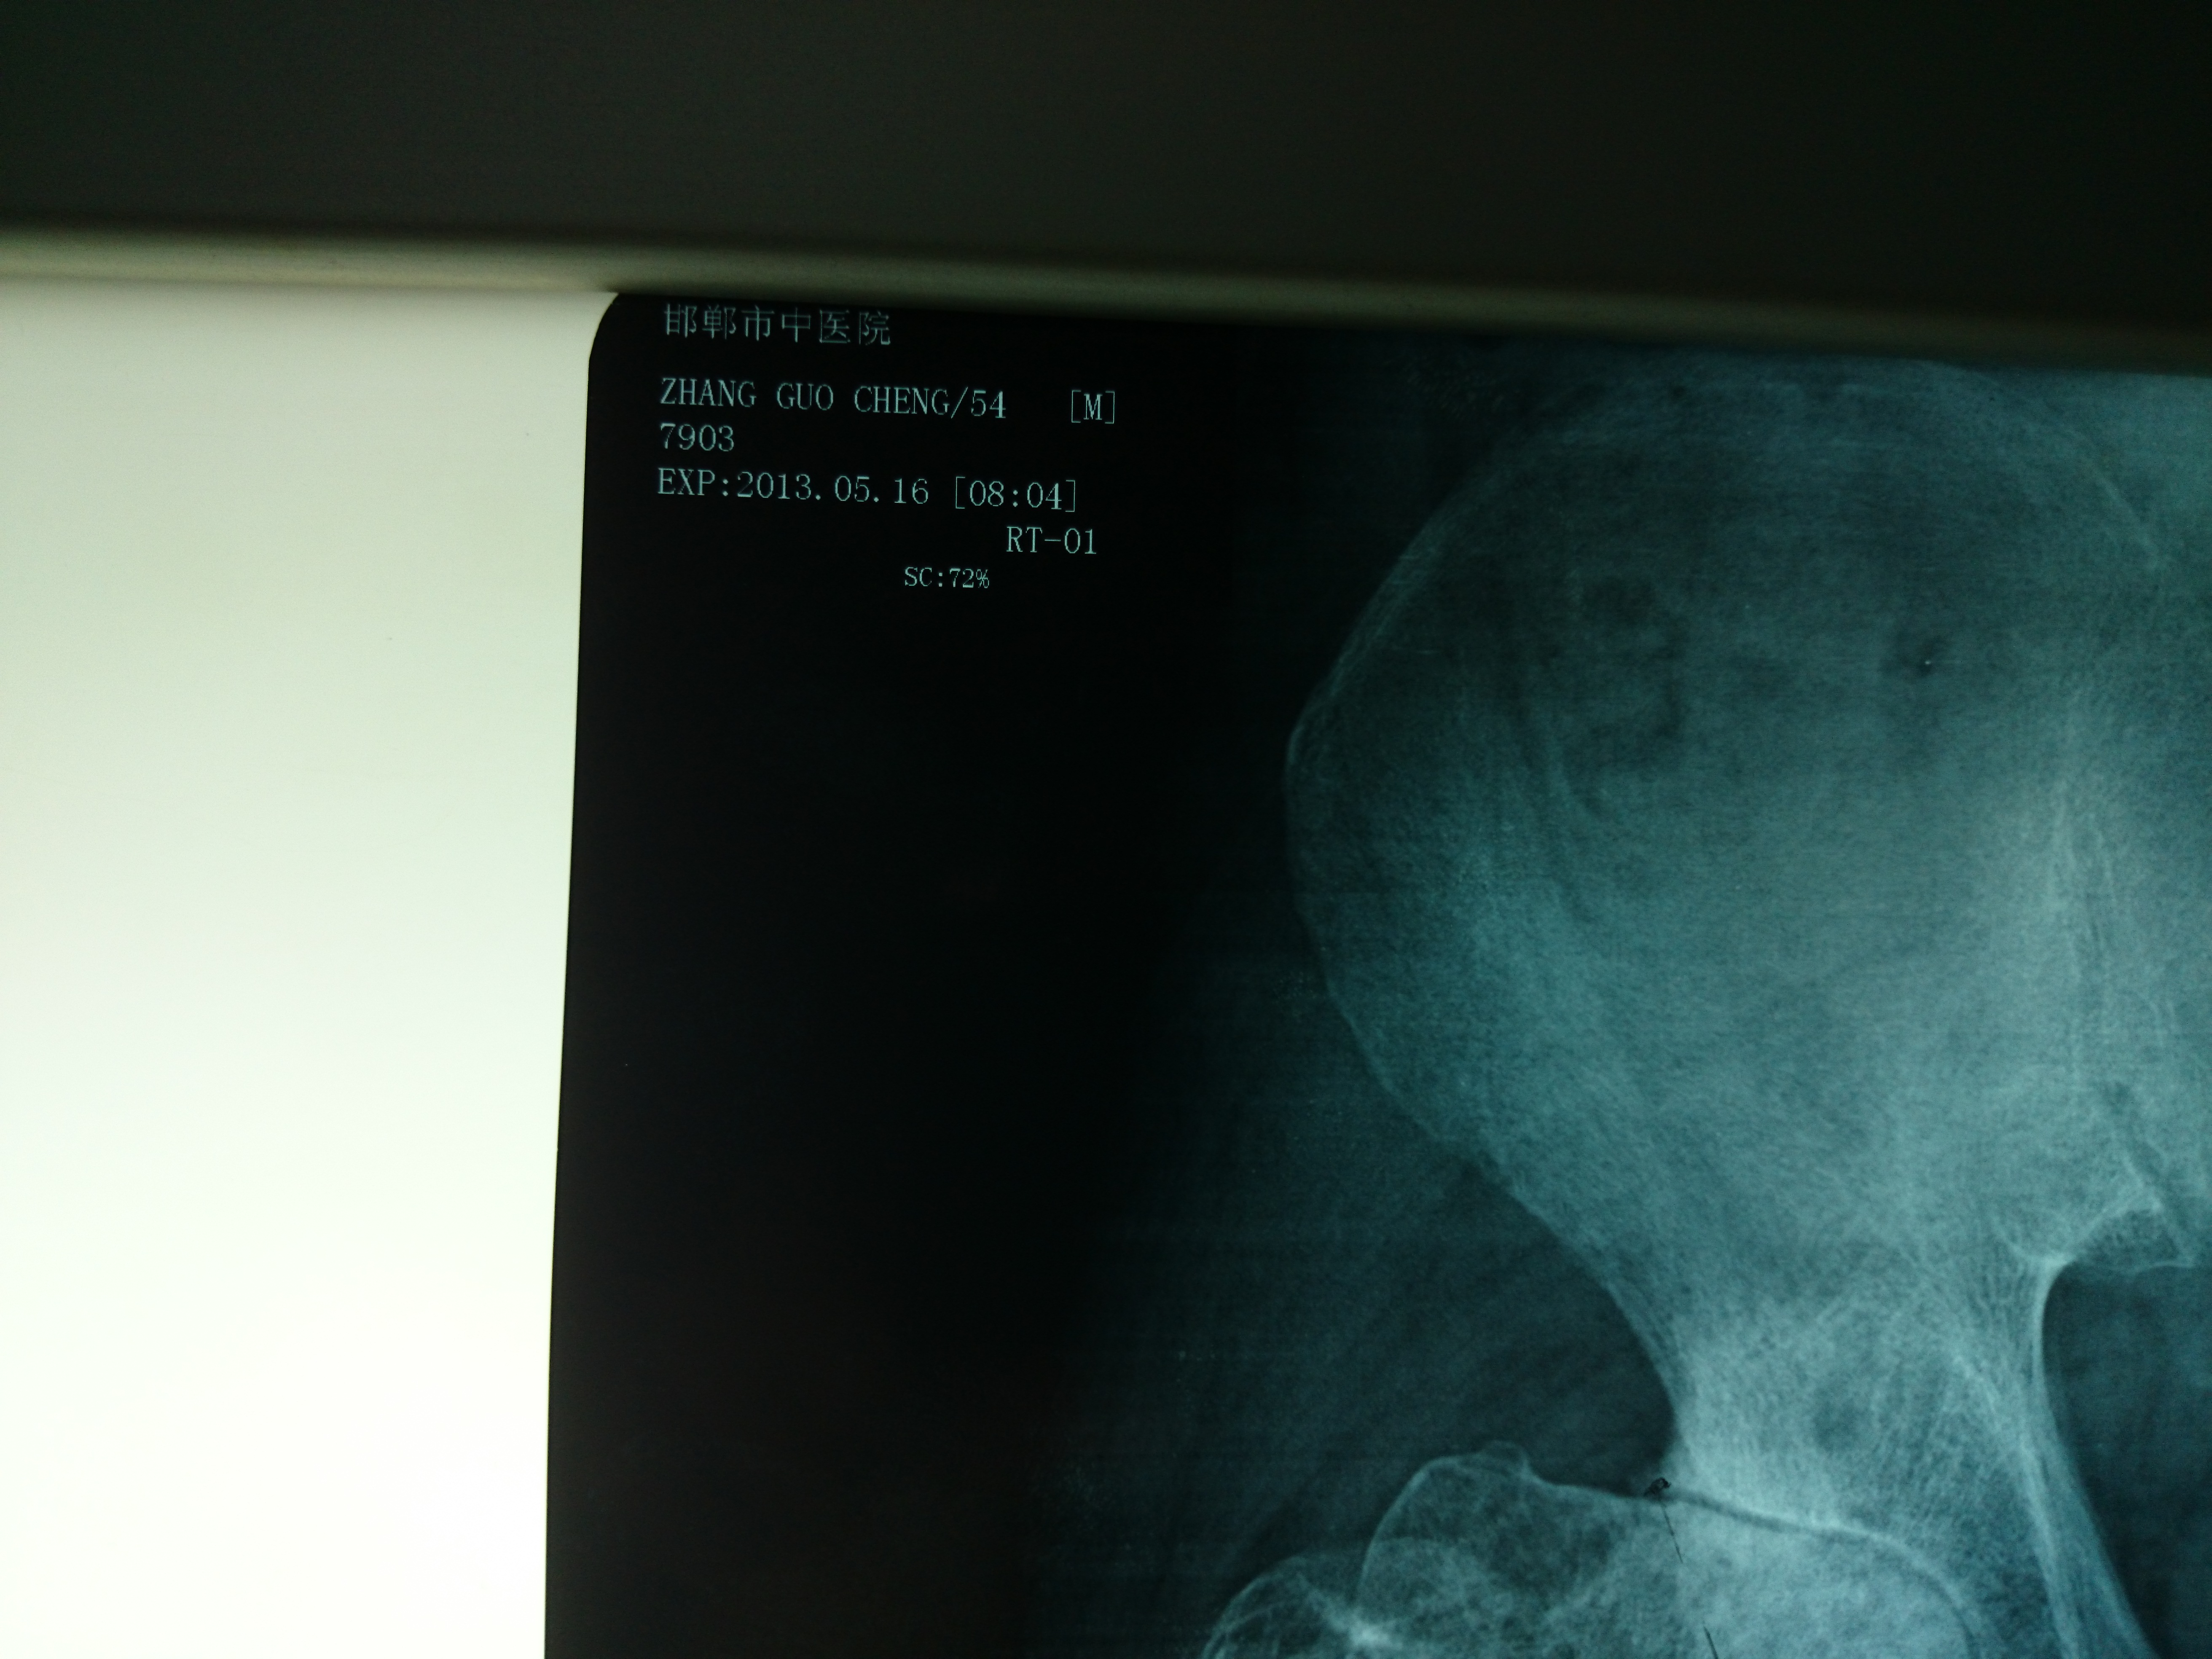

首页 > 张恒云工作室 > 影像资料 二十九